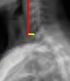

Sagittal Vertical Axis (SVA)

C2-C7 Sagittal Vertical Axis (cSVA) (cervical contribution)